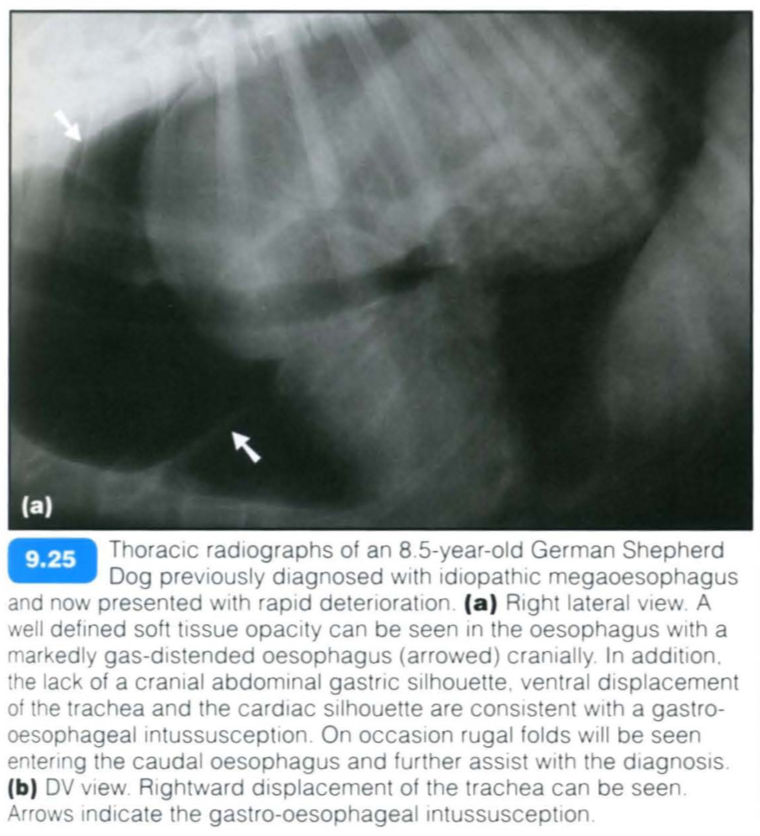

Gastroesophageal intussusception

Gastro-oesophageal intussusception is a condition and results from invagination of the stomach, with or without other abdominal viscera (spleen, duodenum, pancreas and omentum), into the caudal oesophageal lumen.

It has been reported to be more common in younger dogs « 3 months. The highest prevalence has been reported in German Shepherd Dogs or large-breed dogs in general.

The clinical signs include regurgitation, vomiting and distress. Rapid deterioration occurs should a large portion of the stomach prolapse into the oesophagus. This constitutes a surgical emergency with mortality rates in excess of 95%.

Occasionally gastro-oesophageal intussusception may be an intermittent problem.

Radiographic findings include:

Contrast studies: